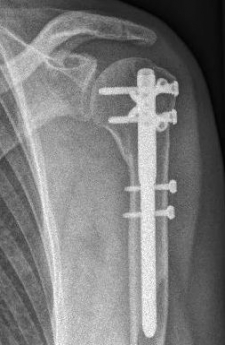

Proximaler Oberarmbruch5Proximaler Oberarmbruch6

Picture: Here is a subcapital upper arm break in a young woman. An angle stable plate osteosynthesis was performed to stabilize the head in correct position to the humeral shaft and shoulder joint. Especially in young patients, We strive to treat non-invasively and as gently as possible. This possibility is often due to the bone quality in young as opposed to older people.